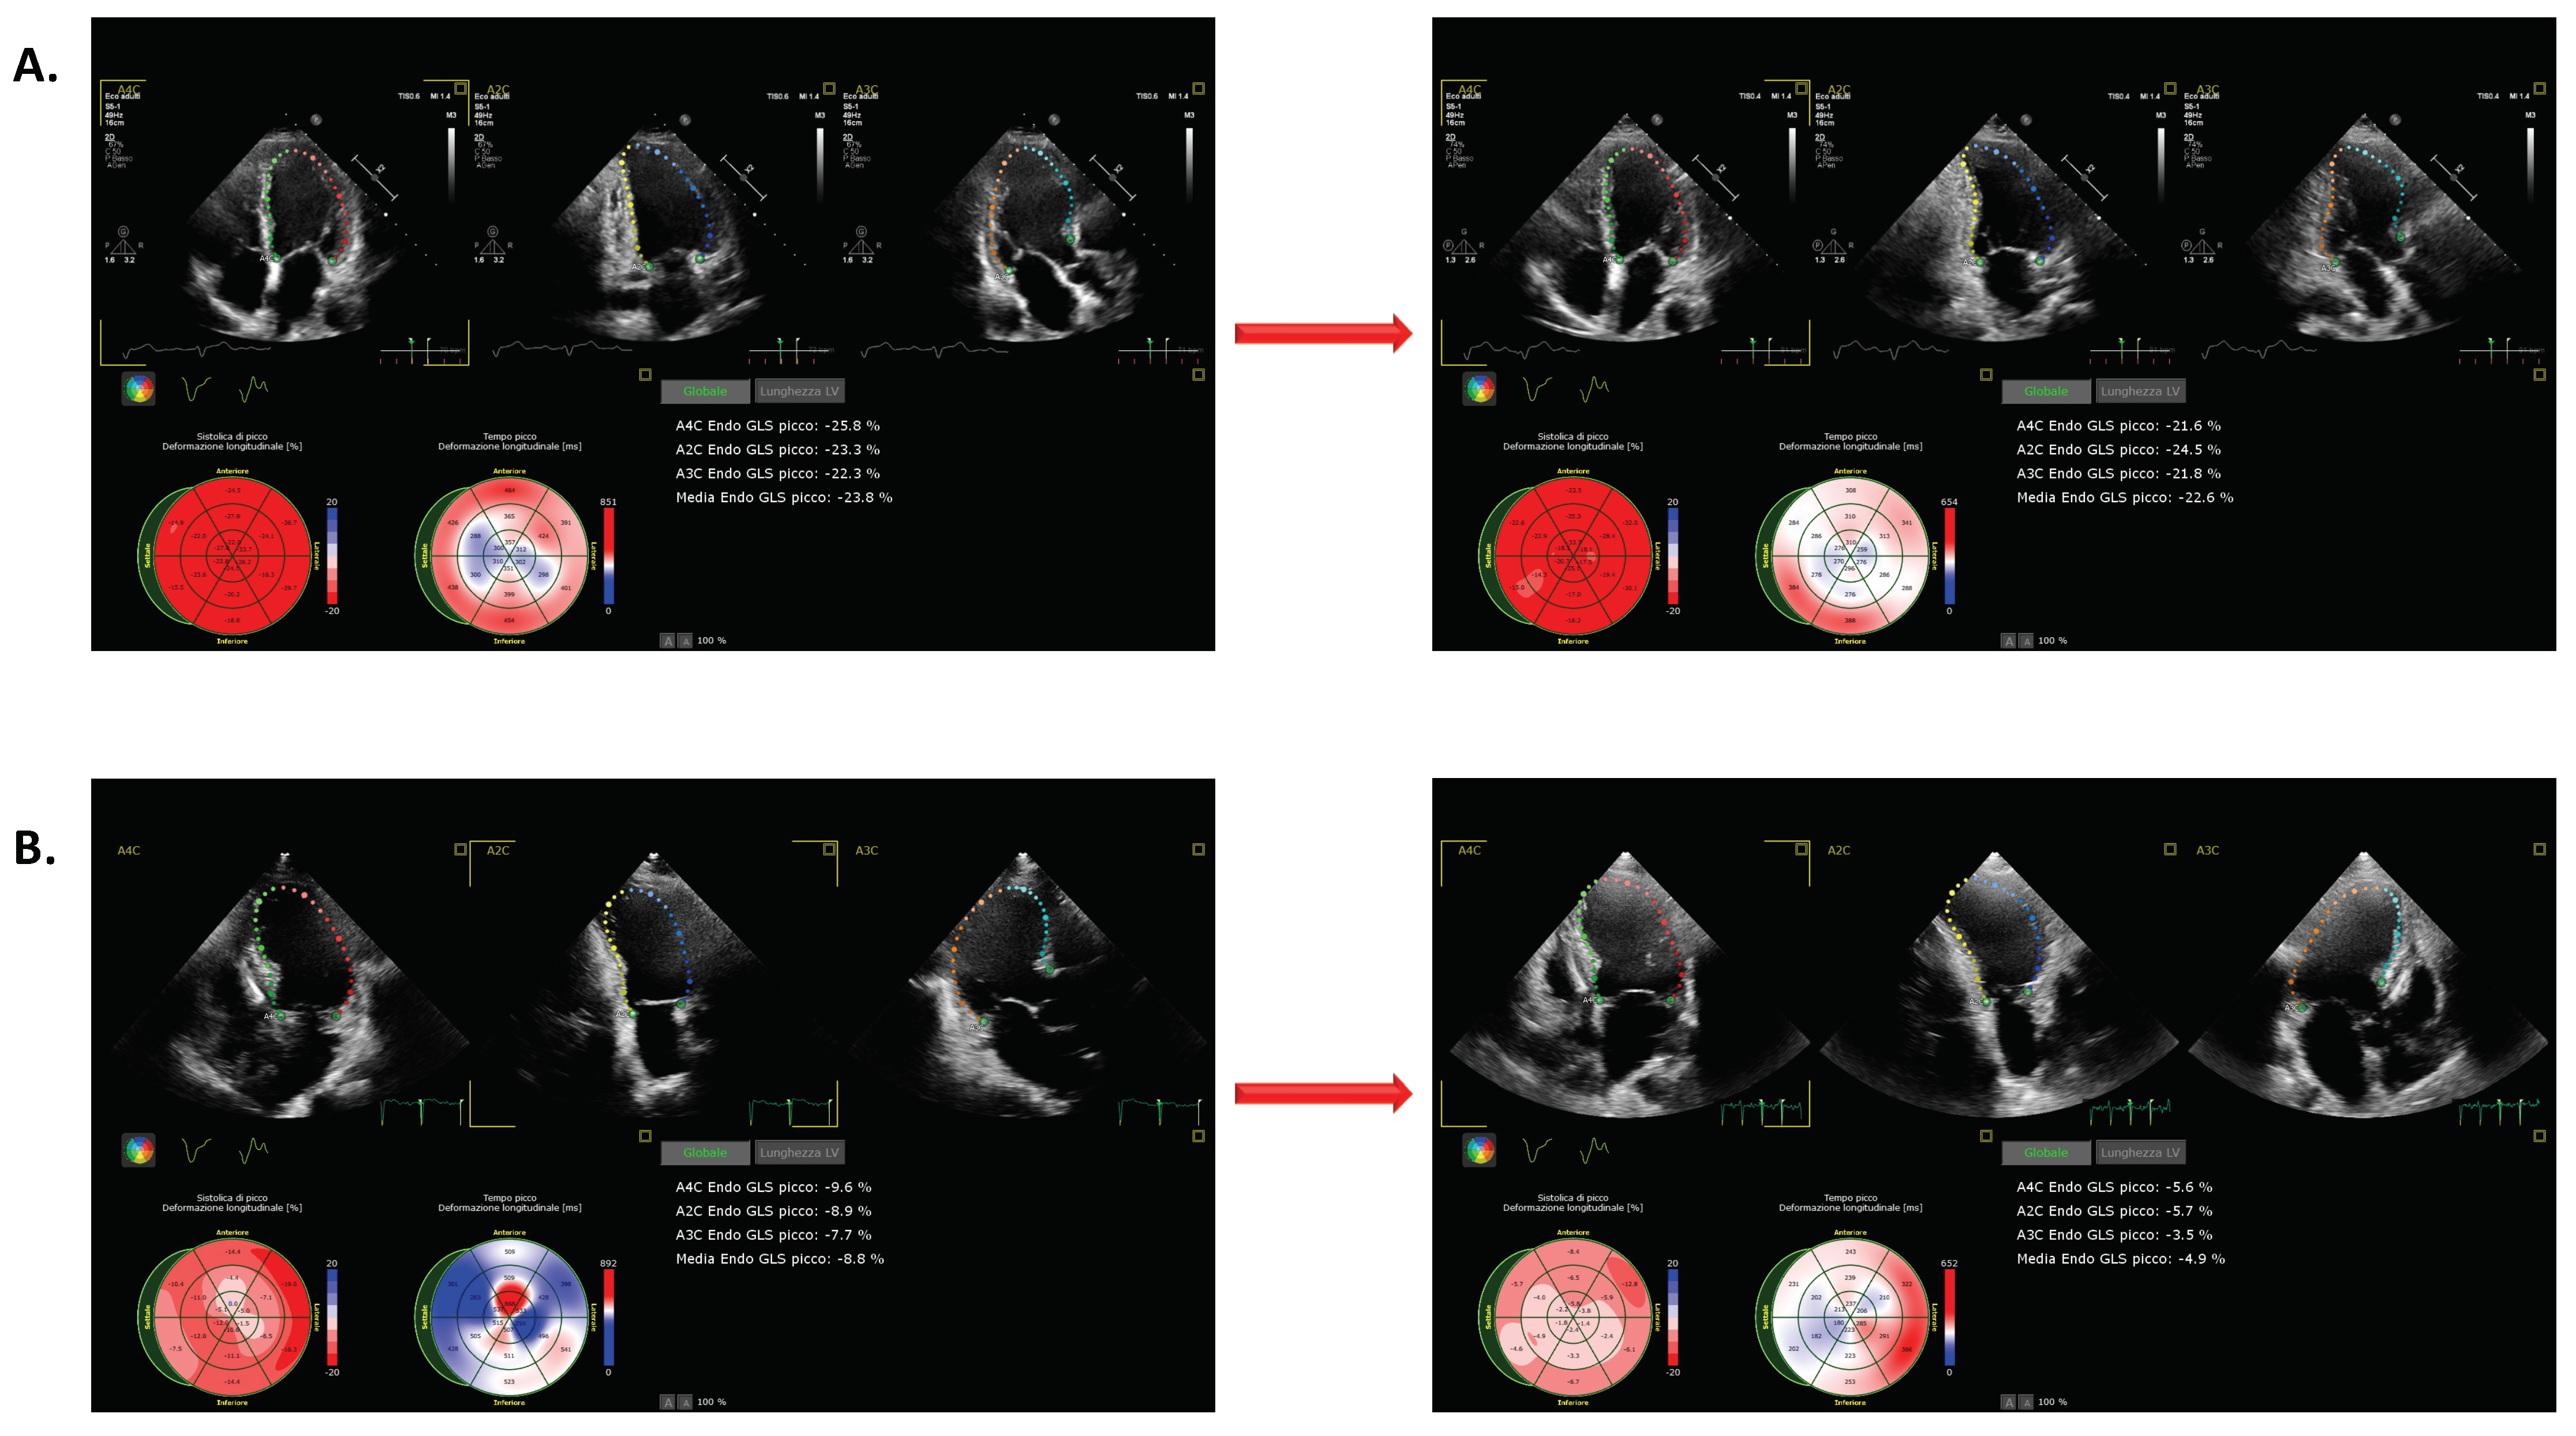

Figure 2.

Two examples of changes in LVGLS. The example in (A) documents improved LVGLS with increasing HR. The example in (B) documents a deterioration in LVGLS in response to increasing HR.

Significant changes in LVGLS were observed overall in response to higher-paced HRs (Figure 1). Thirty-four (76%) patients exhibited deteriorations in LVGLS equal to or greater than 10%; only one patient exhibited some degree of improvement (Figure S1). Figure 1 also documents changes in LVGLS in participants who did and who did not exhibit deterioration in response to an increasing HR. An example of patient with and without worsening of LVGLS is reported in Figure 2. The percentage of participants exhibiting LVGLS deterioration was higher among those managed with an ICD either with or without CRT, at 71% and 86%, respectively, than in participants with PM (57.1%). However, this difference did not achieve statistical significance (p = 0.28). As shown in Table 2, participants with deteriorating LVGLS were those with reduced LV function, as determined by baseline LVEF, LVGLS, and Tei index values.